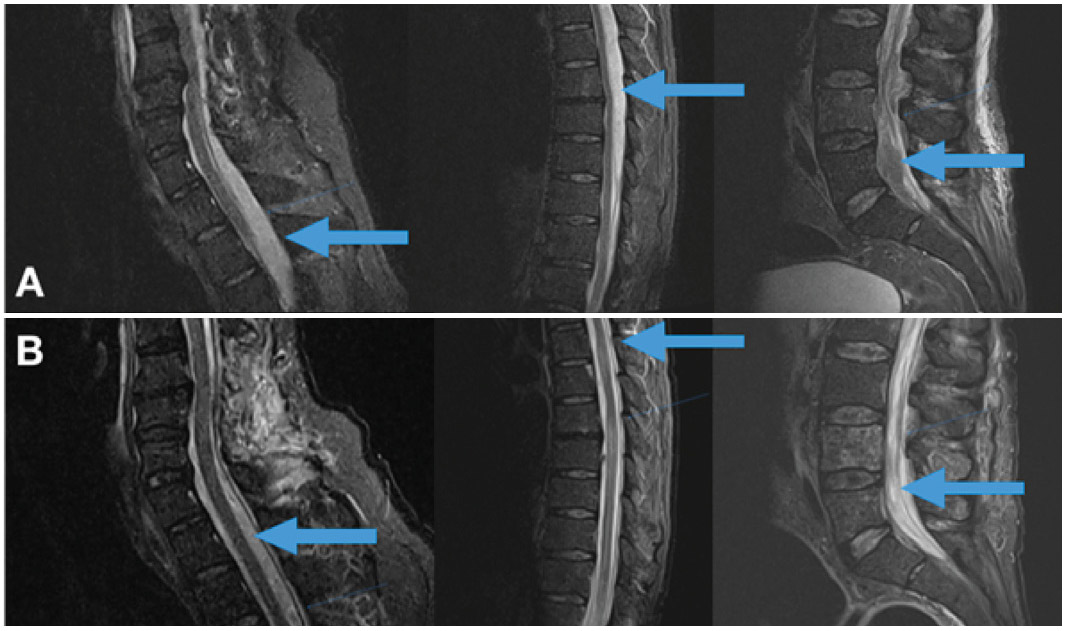

El empiema epidural espinal (EEE) multinivel es una infección rara y grave de la columna vertebral con alta tasa de morbimortalidad. Si bien los abscesos o empiemas de un sector de la columna están bien estudiados, esta patología sorprende por su rareza, reto diagnóstico y terapéutico. Se destaca por ser más frecuente en la edad adulta, en el sexo masculino y se ve asociada a patologías predisponentes.

El agente bacteriológico responsable en la mayoría de los casos es el Staphylococcus aureus. El tratamiento precoz es fundamental y está basado en dos pilares: antibioticoterapia y quirúrgico descompresivo Presentamos dos casos clínicos con afectación multinivel que evolucionaron favorablemente tanto en lo infeccioso como en lo neurológico sin provocar una inestabilidad del raquis y realizamos revisión bibliográfica del tema. Nivel de Evidencia IV; Estudio de Caso-control.